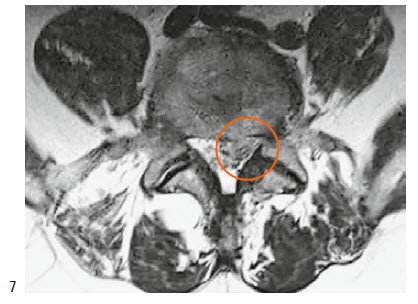

Eine besondere Form der Bandscheibenabnützung ist die Diskushernie (Bandscheibenvorfall) : Wenn die Bandscheibe nicht mehr ausreichend widerstandsfähig ist, wölbt sich ihre äussere Umrandung vor, und es kommt zu einer Bandscheibenprotrusion (Vorwölbung); oder ein Stück der Bandscheibe löst sich von der Bandscheibenmasse und drängt sich aus dem Raum zwischen den Wirbelkörpern in den Nervenkanal heraus. Je nach dem Ort dieses Geschehens können dadurch die Nervenwurzeln des Oberschenkelnervs (Nervus femoralis), des Ischiasnervs und – in ganz besonderen Fällen – die verantwortlichen Nerven für Blasen-, Mastdarmfunktion und Sexualität eingeklemmt und geschädigt werden.

Die häufigsten Bandscheibenvorfälle finden sich innerhalb des lumbalen Spinalkanals. Sie verdrängen die Nervenwurzel nach hinten in die Mitte oder in den seitlichen Anteil des Spinalkanals (mediolaterale Diskushernie). Durch einen kleinen vertikalen Schnitt von ca. 2 cm in der Mitte des Lendenbereichs wird der Bogen des Wirbels freigelegt. Durch eine schonende Abtragung eines kleinen Knochenstücks am Wirbelbogen und Öffnung des gelben Bandes wird der Anteil der Bandscheibe, der auf die Nervenwurzel drückt, sorgfältig entfernt. Dieser Eingriff erfolgt in der Regel unter mikroskopischer Kontrolle (Abb. 4).